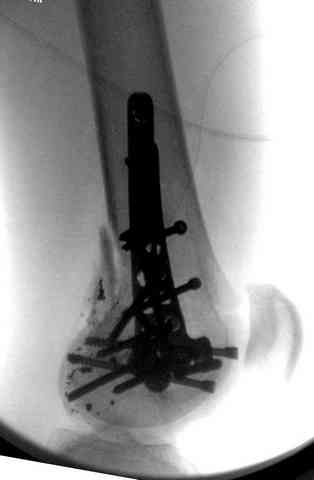

Здесь представлены несколько случаев лечения огнестрельного перелома

3 сегментарный перелом бедра с переломом Хоффа фрагментом, сделано из минимального доступа